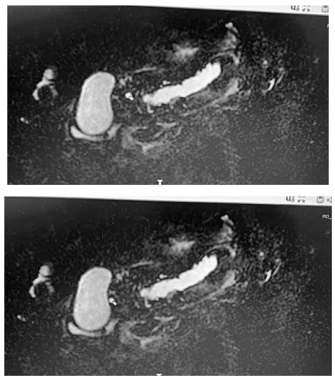

Uma mulher de 62 anos de idade, com dor epigástrica de leve intensidade há seis meses, não teve melhora significativa com o uso de sintomático, porém também não teve agravamento dos sintomas. Nega emagrecimento e não tem outras queixas significativas. Histórico familiar negativo para câncer. Nega tabagismo ou álcool. Fez endoscopia digestiva normal. Exame de sangue específico: leucograma 10 mil/mm3 ; glicemia 110; amilase 320; lipase 200; CEA 1.2; Ca 19.9 16; e bilirrubina total 0,9. Apresentou o exame abaixo, uma ressonância pancreática.

Com base nesse caso hipotético, assinale a alternativa que apresenta a melhor orientação.